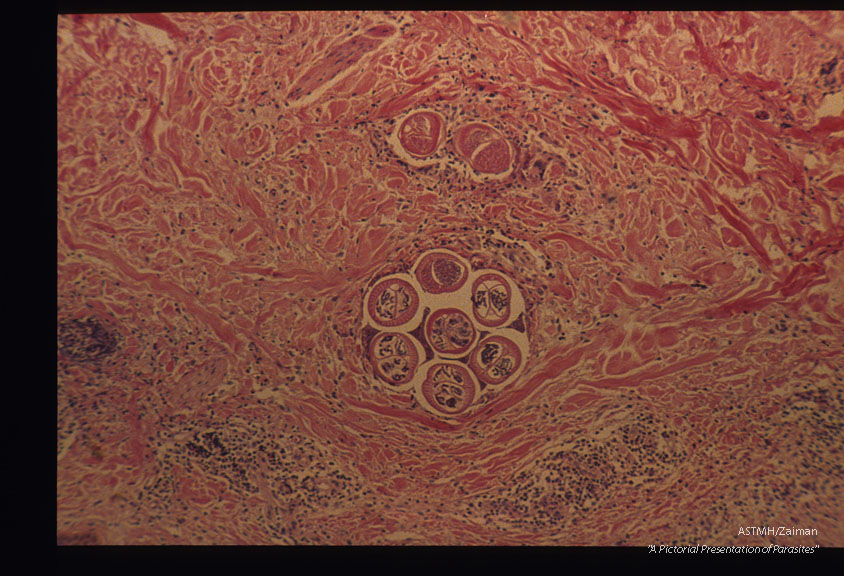

Section of skin with worms. H & E. Low and high magnifications.

Dipetalonema streptocerca

Description: Section of skin with worms. H & E. Low and high magnifications.